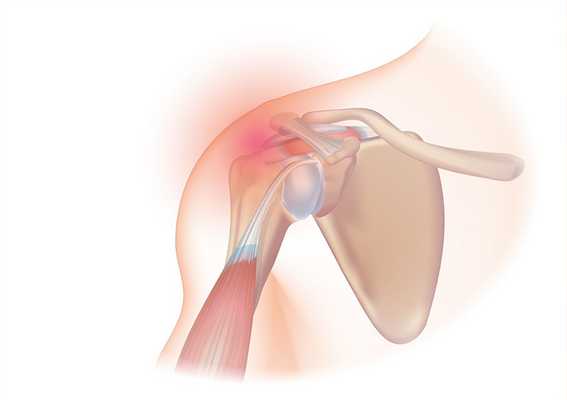

в) Хирургическая анатомия:

• Ротаторная манжета: сухожилия надостной, подостной, подлопаточной и двуглавой мышц:

• Депозиты кальция обычно не контактируют с зоной прикрепления сухожилий, находясь от нее на расстоянии по меньшей мере 1,5-2 см (Uhthoff и Loehr, 1997)

• На рисунке 2 показан плечевой сустав сбоку (рис. 2, А) и спереди (рис. 2, Б) и обозначены ротаторная манжеты и возможные участки кальцификации

• Распределение депозитов кальция: надостная мышца (наиболее часто) > подостная мышца > подлопаточная мышца (Gosens и Hofstee, 2009; Jerosch et al., 1998):

В надостной мышце депозиты локализуются в 51-90% случаев (Gosens и Hofstee, 2009)

В подостной мышце — около 6% (Jacobs и Debeer, 2006)

В подлопаточной — 3% (Gosens и Hofstee, 2009)